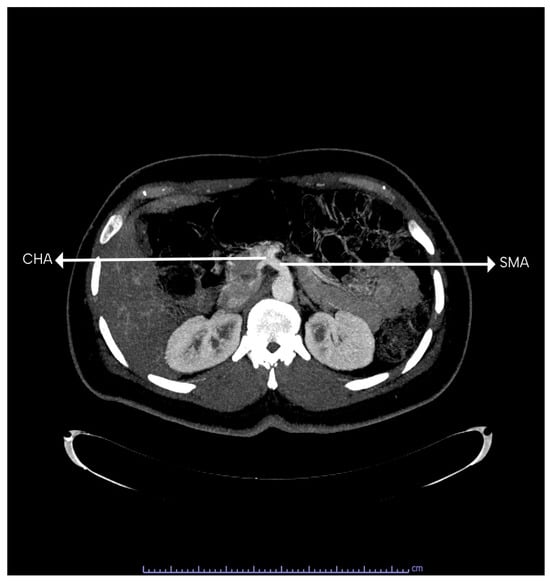

The CT normally trifurcates into the left gastric, splenic, and common hepatic arteries. Figure 5 shows the 3D construction of the normal branching of the CT. The CT showed classical trifurcation in 112 (96.60%) patients, where it divided into the splenic artery, left gastric artery, and the common hepatic artery. In the other four patients, bifurcation of the CT was observed. In two (1.70%) out of the four patients (one male and one female), the CT gave rise to the splenic and left gastric artery (gastrosplenic trunk; Uflacker’s type V), while the common hepatic artery took origin from the superior mesenteric artery. Figure 6 shows a common hepatic artery originating from the superior mesenteric artery. In the other two patients (1.70%) (one male and one female), the CT gave rise to the splenic and common hepatic artery (hepatosplenic trunk; Uflacker’s type II), while the left gastric artery arose as a direct branch from the abdominal aorta. Figure 7 shows the left gastric originating from the abdominal aorta, while the CT bifurcates into the SA and common hepatic artery.

Figure 6. A computed tomography scan showing common hepatic artery (CHA) taking origin from the superior mesenteric artery (SMA).

Figure 7. A computed tomography scan of a patient in sagittal and axial view. In the sagittal view, it is shown that the left gastric artery (LGA) takes direct origin from the abdominal aorta. In the axial view, it is shown that the celiac trunk (CT) branches into the splenic artery (SA) and the common hepatic artery (CHA) branches into the superior mesenteric artery (SMA).